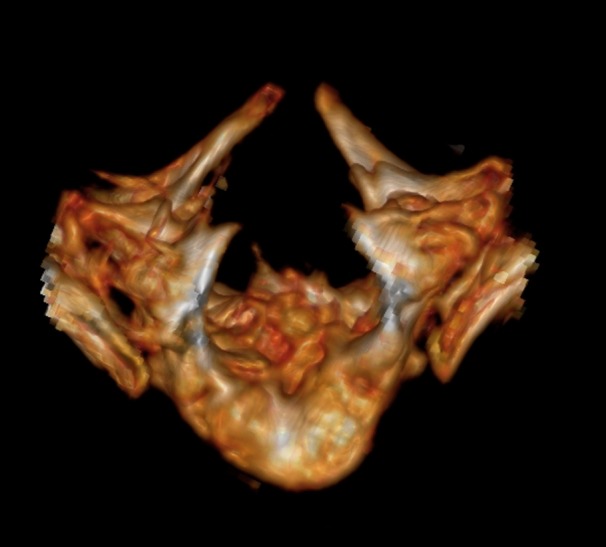

The skin of all the subjects had signs at the region of the back, similar to local hypertrichosis, hemangiomas, or skin dimpling (a representative image is shown in Fig. 2). Widening of the interpedicular distance at the level of one or a few vertebral segments is a very distinctive feature for patients with diastematomyelia as shown in Fig. 3. In such cases, the presence of spinal cord splitting was clearly visualized on MRI (Fig. 4). CT images provided the necessary information to differentiate between bony and fibrotic septum (Fig. 5). In our population, 18 (90%) subjects had different types of congenital vertebral anomalies, including failure of formation, segmentation and a combination of aforementioned, while 17 (85%) subjects had congenital scoliosis. In 2 (10%) subjects with fibrotic septum, there were no congenital abnormalities. The most commonly seen musculoskeletal deformity in subjects with diastematomyelia was lower limb asymmetry. Atrophy with increasing muscle weakness was thought to be a case of neurological deterioration, thus being an indication for surgery. Partial restorations of neurological function were observed in total four subjects, for whom spur resection surgery was carried out.

Fig. 5.

3D reconstruction of the CT showing two bony spuns in the vertebral canal. Diastemas of such extension are quite rare